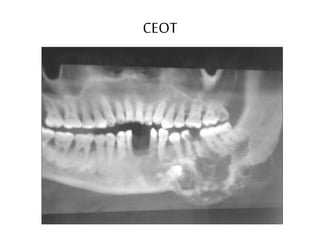

2- Calcifyingepithelial odontogenictumor (CEOT)=

Pindborgtumor

CEOT

Unilocularor Multiocular+ RO Foci

• 40 y.

• Males

• Mand. Molar Ramus area

• Mostly Related to impacted/ unerupted tooth (50%)

• Calcific foci are numerous closely located to the crown

(snow driven appearance)

• Sever expansion (less than ameloblastoma) +

maintenance of cortical boundaries

• Teeth Displacement

Rare tumor